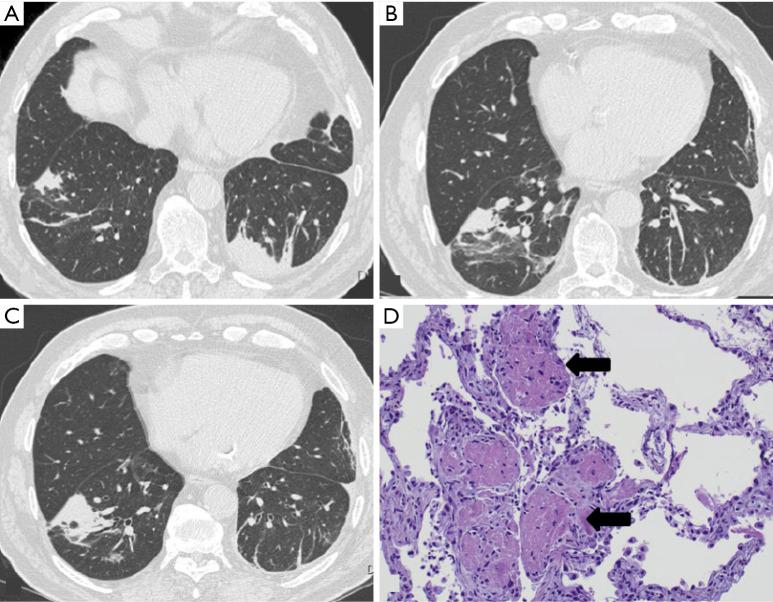

BACKGROUND AND OBJECTIVE

Interstitial lung diseases (ILDs) encompass over 200 entities. Among them, fibrosing lung diseases, have recently generated special interest due to the emerging therapies for their management. However, it is important to deepen our knowledge of other less prevalent ILD, since many of them are associated with a poor prognosis. This narrative review aims to provide a practical and up-to-date description of some poorly recognized ILD. It covers rare idiopathic interstitial pneumonias and their histologic patterns, genetic disorders with interstitial lung involvement (Hermansky-Pudlak syndrome), and ILD associated with benign proliferation of pulmonary lymphoid tissue, namely follicular bronchiolitis and granulomatous-lymphocytic interstitial lung disease.

KEY CONTENT AND FINDINGS

Despite the low prevalence of these diseases, the increased recognition of radiological patterns, pathological features, and diagnostic procedures, have permitted their better characterization. This review highlights epidemiology, clinical presentation, diagnosis, natural history, and treatment.